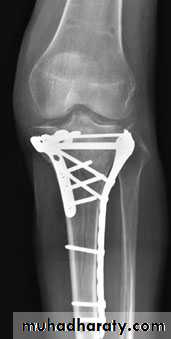

Undisplaced fractures treated conservatively: Haemarthrosis aspiration and compression bandaging,above knee cast for one months followed by functional brace and physiotherapy.For displaced fractures treatment is by open reduction and internal fixation with plate and screws as it is an intra articular fracture.

fixation of tibial plateau fracture